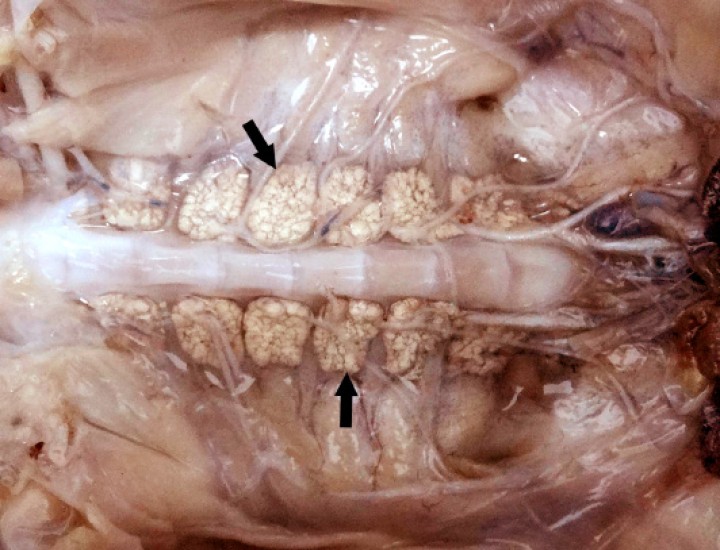

<p>Sapillo balear (<em>Alytes muletensis</em>). Los riñones contienen masas amarillentas-blanquecinas correspondientes a adenomatosis renal (flechas). Paciente fijado en formol. Barra: 1 cm.</p>

Figura 11

Sapillo balear (Alytes muletensis). Los riñones contienen masas amarillentas-blanquecinas correspondientes a adenomatosis renal (flechas). Paciente fijado en formol. Barra: 1 cm.

Se observaron 8 neoplasias, diagnosticadas en 6 de los 131 (4,6%) anfibios. Dos correspondían a adenocarcinomas sin evidencias de metástasis: uno intestinal en una rana dardo verdinegra (Dendrobates auratus) (Fig. 8), y otro en un tejido no identificable en un sapo buey (Rhinella schneideri); este último mostraba, además, hemangiomas en el pulmón (Fig. 9). El adenocarcinoma intestinal de la rana dardo verdinegra (Dendrobates auratus) consistía en una proliferación mal delimitada y no encapsulada de enterocitos que formaban criptas y glándulas variablemente dilatadas o, raramente, nidos diminutos compactos que invadían de forma amplia todas las capas del segmento intestinal afectado (Fig. 8) y mostraban anisocitosis, anisocariosis, pleomorfismo y anaplasia bajos a moderados, sin actividad mitótica aparente. Otros 3 anfibios padecieron neoplasias hematopoyéticas: un linfoma multicéntrico con componente epiteliotrópico en una rana tomate (Fig. 10) y dos neoplasias de células redondas no identificables de forma clara mediante la tinción rutinaria en un sapillo balear (Alytes muletensis) y un axolote (Ambystoma mexicanum). Otro sapillo balear (Alytes muletensis) mostraba una proliferación multicéntrica benigna de epitelio renal tubular (Fig. 11) organizado en estructuras tubulares, papilares y quísticas (Fig. 12), compatible con adenomatosis renal (adenomas múltiples); se observó atipia celular en escasas células neoplásicas y en células epiteliales de túbulos no neoplásicos. Adicionalmente, en este sapillo balear (Alytes muletensis) se apreció un foco hepático bien delimitado y no encapsulado de proliferación de hepatocitos compatible con hiperplasia nodular o un hepatoma; la ausencia de tríadas portales dentro de esta neoplasia es compatible con un hepatoma (Fig. 13).